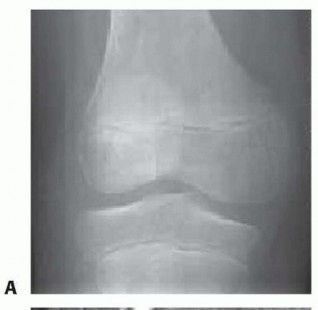

Chapter 40 Arthroscopic Treatment of Elbow Loss of Motion Laith M. Al-Shihabi Chris Mellano Robert W. Wysocki…